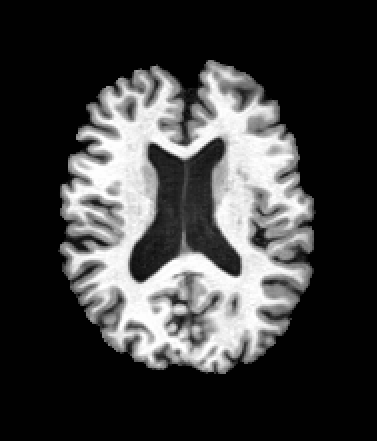

A distinctive strength of MetaVoxel is its ability to perform flexible zero-shot inference for a broad spectrum of tasks with arbitrary subsets of inputs. To enable this, we reinterpret the RePaint strategy described in Section 2: just as RePaint performs conditional image generation by specifying a binary mask that marks which pixels are fixed, we can further designate any subset of MetaVoxel’s variables as “known” conditions. At each denoising step, these known variables are overwritten with their re-noised values, ensuring that they remain fixed throughout the sampling trajectory, while the remaining variables evolve according to the learned reverse process. This keeps the synthesized variables consistent with the conditioning, analogous to how RePaint produces inpainted regions consistent with the known region. Although MetaVoxel learns the joint distribution , different downstream tasks can be realized simply by choosing which variables to fix during sampling. Image inpainting is achieved by fixing pixel regions of the image variable***see examples in Appendix (Figure B.2); conditional image generation by fixing variables such as age or sex; regression tasks (e.g., age estimation) by fixing any combination of image and sex; and classification tasks (e.g., sex prediction) by fixing any combination of image and age. As more variables are included in the joint model, the range of possible zero-shot tasks naturally expands. For example, when multiple imaging modalities are present, fixing one modality and sampling the other enables image-to-image translation.

| Input | Inpainting with Left Half of the Image Fixed | ||||

|---|---|---|---|---|---|

![]() |

|